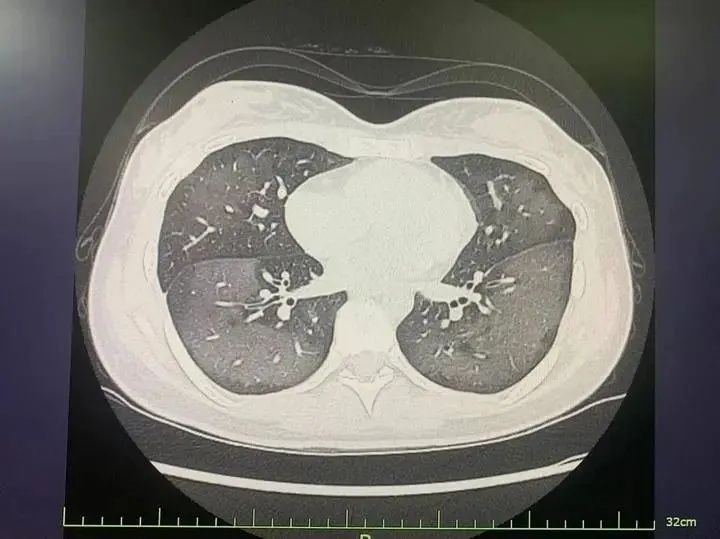

陈国庆副主任医师接诊后,迅速为涵涵安排了简单的血检和胸片检查,胸片结果提示两肺大片斑片影,已接近“白肺”,血常规则提示白细胞升高、C反应蛋白正常。

陈国庆了解了涵涵的病史并结合临床表现,基本考虑是防晒喷雾吸入后导致急性过敏性肺炎。

起病还不到一天,涵涵的胸片所提示的肺部病变为什么会如此广泛且弥漫?陈国庆说,“这是急性过敏性肺炎的典型表现,来势通常较为凶猛,如果不及时就诊,可能会发展为重症肺炎,出现呼吸衰竭等情况,危及生命。”